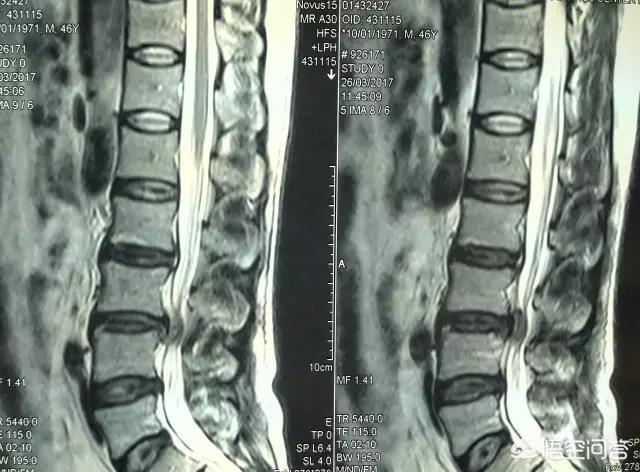

在各种原因导致的腰椎管狭窄的基础之上,我们走路的时候会导致椎体和神经根的压力负荷增大,进而导致狭窄相应部位微循环障碍,出现缺血性神经根炎。所以走一段之后,就会出现腰酸腿痛、下肢无力发麻,出现跛行的症状,但是坐下或者躺下休息一会之后,神经根的压力负荷减轻,狭窄相应部位微循环得以改善,症状就会逐渐缓解或消失,可以继续行走,再走一段路之后又再次出现上述症状,如此反复。